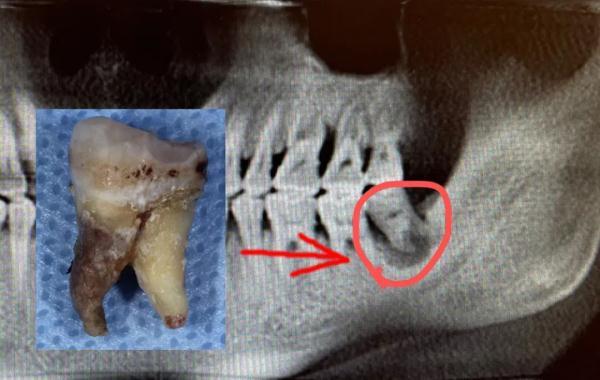

陳申國說,這么嚴重的感染,一般要兩個星期才能恢復(fù),蔣先生的身體確實好,才一個多星期,病灶處的膿液已經(jīng)排得差不多了,可以拔除那顆病牙了。

問題牙齒